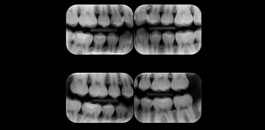

Interproximal

Indicada para avaliação detalhada das estruturas interproximais.